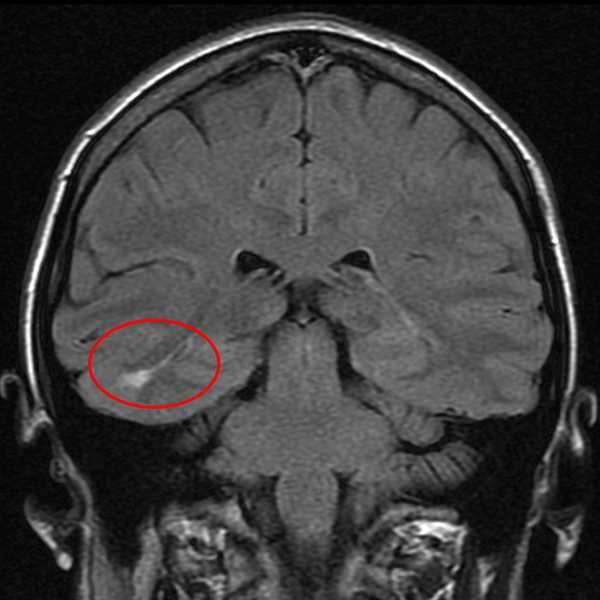

Even though Dravet Syndrome has onset during infancy and may occur following illness or inoculation, there is strong evidence to suggest that its developmental roots lie within the early prenatal period. Le Gal et al. (2010) reported on a child with Dravet Syndrome who was positive for SCN1A mutation. On postmortem study, the researchers found that this child had a type of brain malformation common to epilepsy called a focal cortical dysplasia. Focal cortical dysplasias are strong evidence of early disturbances to the formation of the brain, suggesting that even though seizures don’t occur in Dravet’s until infancy or early childhood, the brain malformations that lead to the condition are formed during pregnancy.

A patient with epilepsy and a focal cortical dysplasia within the temporal lobe. Borrowed from here.